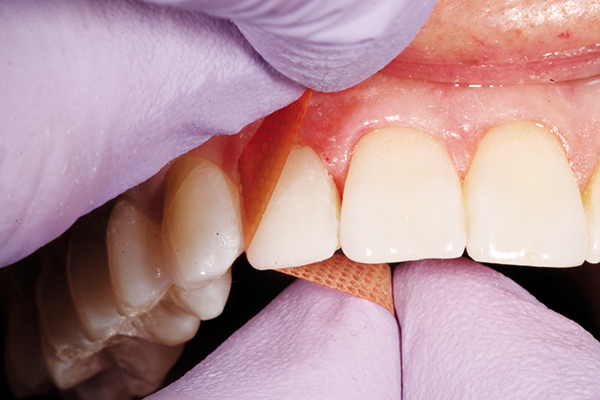

ONE COAT 7 UNIVERSAL (COLTENE) bonding agent was applied/dried for 25 seconds and cured for 10 seconds (Fig. 7). Using a putty matrix, a thin layer of translucent shade was adapted and sculpted to create a lingual incisal “scaffold” to frame the primary anatomy of the tooth as well as the lingual occlusal anatomy (Fig. 8).

Fig. 8 Fig. 9

The A1/B1 Duo Shade was applied and layered using a compule of material on the facial surface following the two planed anatomy of the tooth as well as the mesiodistal line angles of the contralateral tooth and buccal contours of the adjacent teeth (Fig. 9).